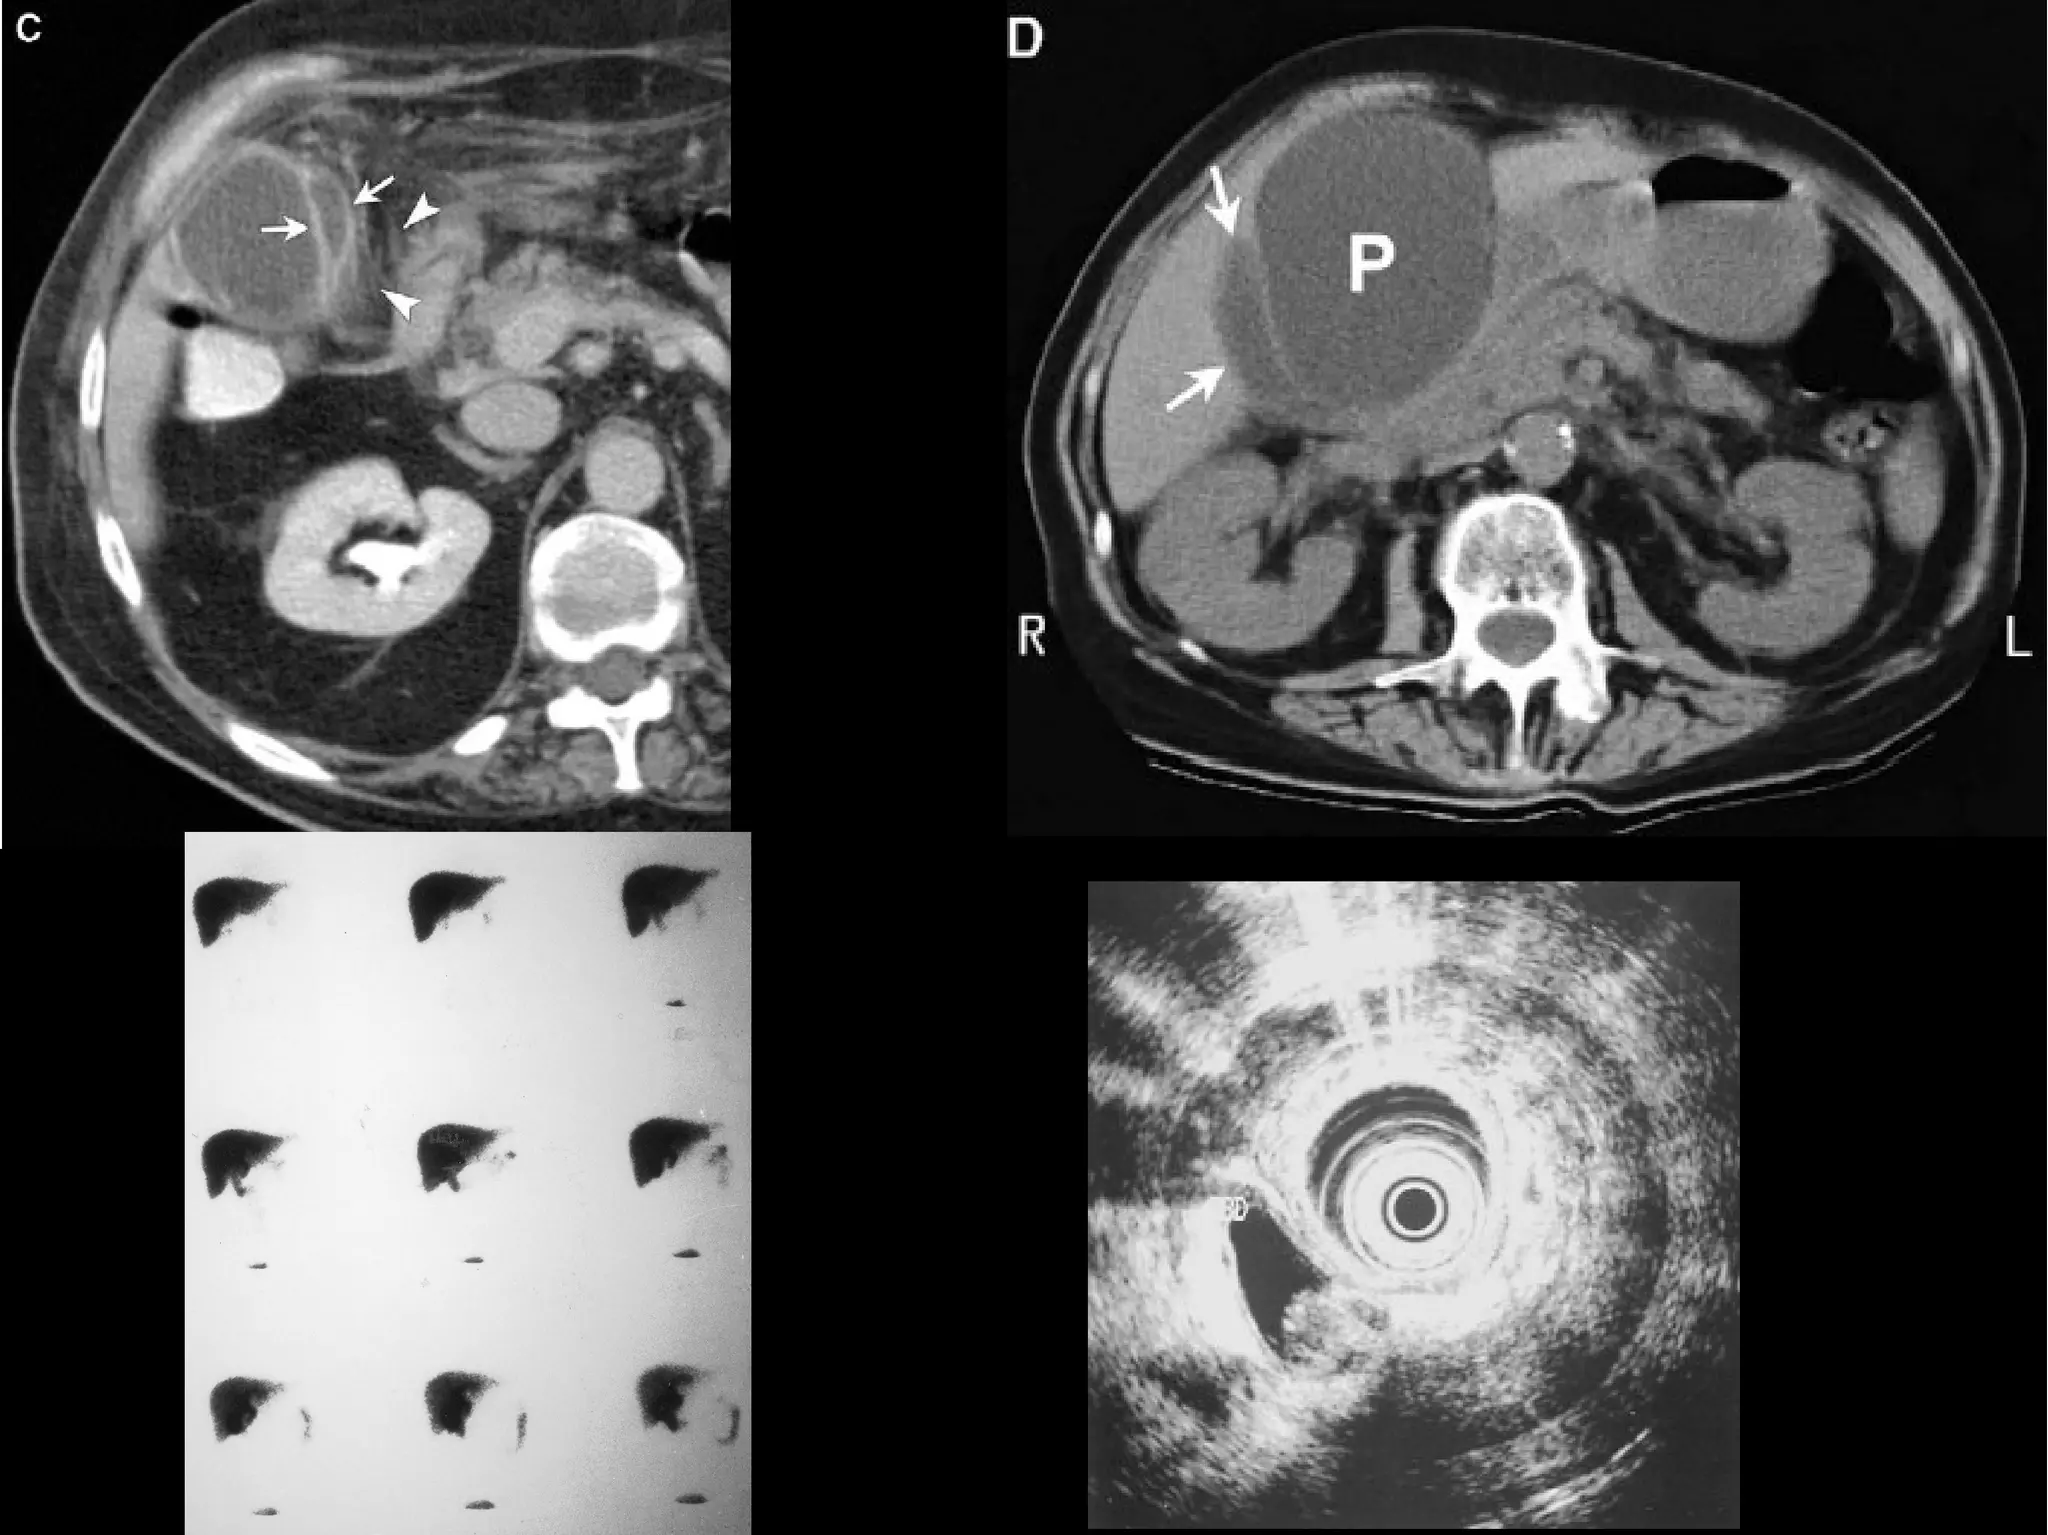

• #6 Aspecto macroscópico de vesícula biliar después de seccionarla longitudinalmente. Notar el engrosamiento de la pared, abundantes cálculos polihédricos y un pequeño tumor papilar en el conducto cístico. Proliferacion papilar de la mucosa biliar Nervio periferico infiltrado por adenoca vesicula biliar Caracteristicas histologicas del adenocarcinoma

• #18 CT shows an enhancing rim around the fluid (arrows) and inflammatory edema in the adjacent fat (arrowheads). (D) CT of the pancreatic pseudocyst (P) displacing the gallbladder (arrows). HIDA SCAN normal, capta medio de contraste Ultrasonido endoscopico con litos en la vesicula biliar